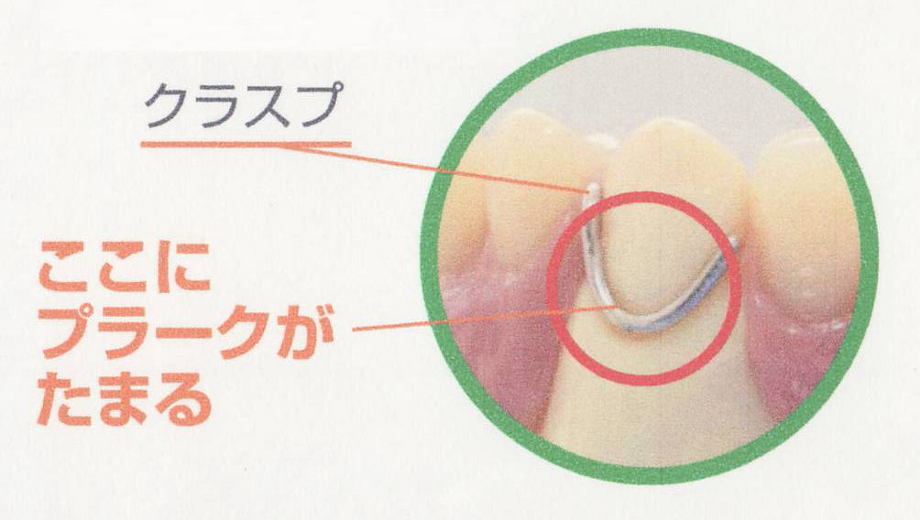

平成25年11月17日(日)名古屋駅 ウィンク愛知会議室にて、アイキャストシンポジウム2013-今、なぜパーシャルデンチャーなのか?-の講演会を受講してきました。

第一部:快適なパーシャルデンチャーを求めて

第二部:ノンメタルクラスプデンチャーから見るパーシャルデザイン

第三部:臨床例解説

でありました。

部分入れ歯の特に、針金の目立たない入れ歯の設計が主なメインテーマで、

とても参考事例が数多く、とても勉強になり、あすからの診療に役立てたいと思います。